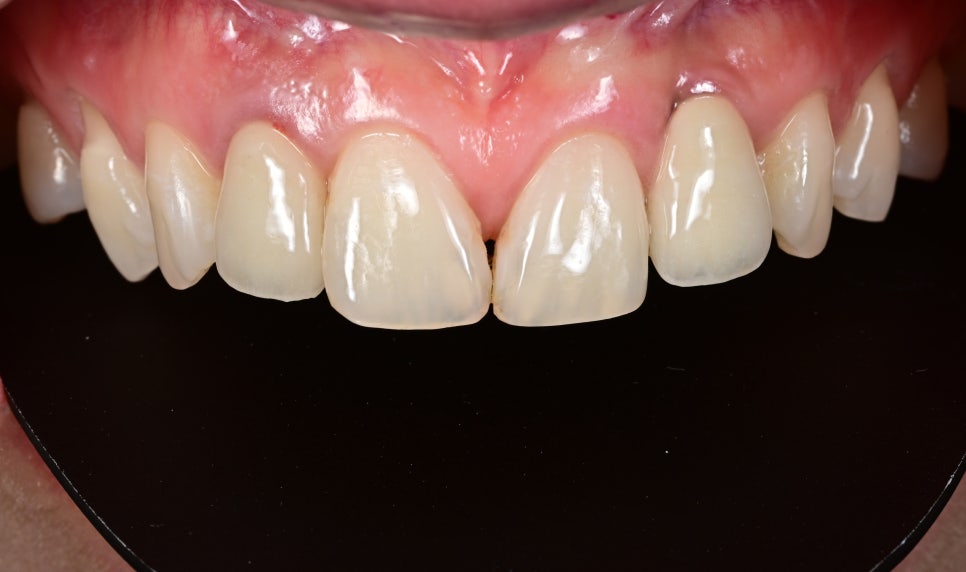

라미네이트, 임플란트 시술 전

- 기존 임플란트 보철의 어색한 부분 개선

앞니 임플란트는 자연치와 달리 빛 투과감이나 잇몸과의 연결감에서 차이가 나기 쉬워 보철 디자인이 매우 중요합니다.

기존 보철의 색감과 형태, 조화도를 다시 점검하여 주변 치아와 보다 자연스럽게 이어지도록 보철을 재설계했습니다.

- 오브제로 라미네이트를 통한 전반적인 심미 조화 개선

임플란트만 단독으로 수정하면 오히려 주변 자연치와의 차이가 더 도드라질 수 있기 때문에, 전체 앞니 라인을 고려하여 오브제로 라미네이트를 함께 진행했습니다.